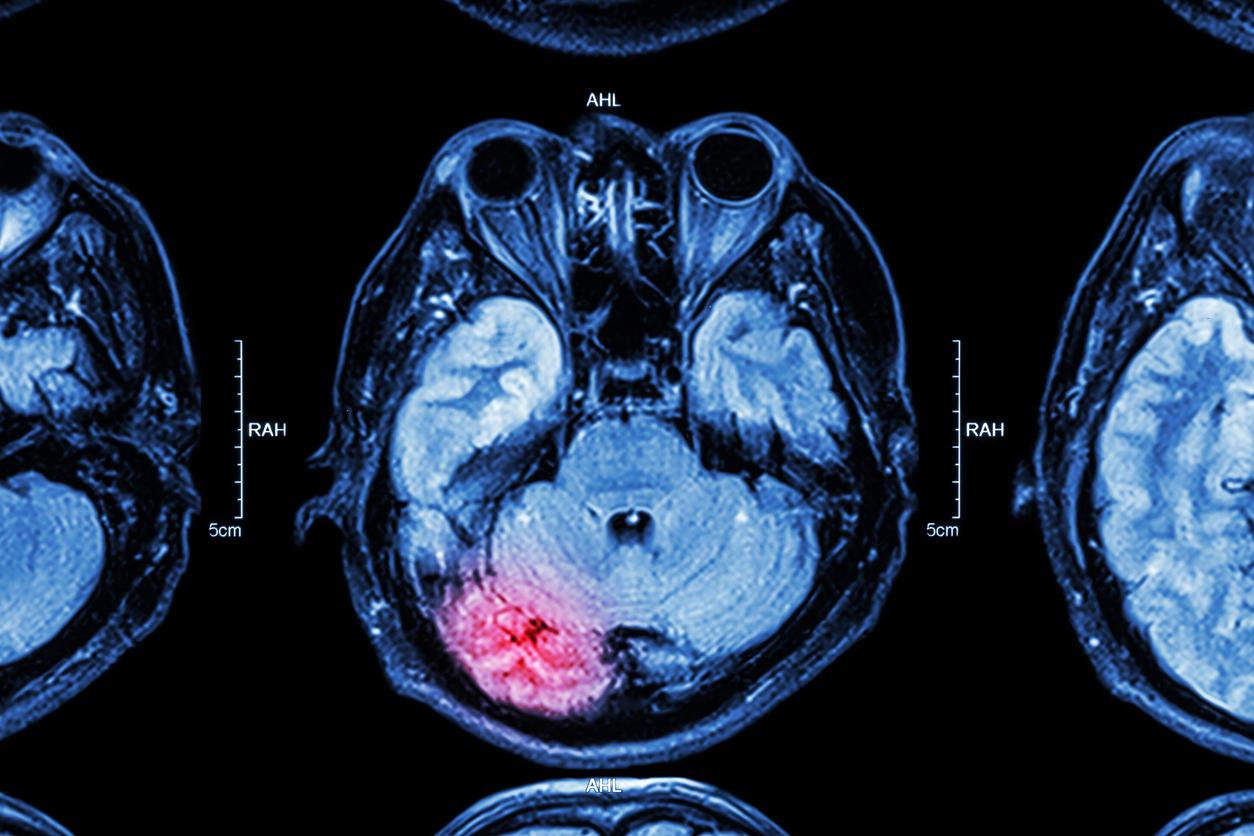

Le gliome est un type rare, mais agressif, de cancer au cerveau. Il survient dans les cellules gliales telles que les astrocytes. Ces dernières sont pourtant considérées comme "moins susceptibles de provoquer des tumeurs", expliquent les chercheurs du University College London Cancer Institute dans un communiqué. "Cependant, des découvertes récentes ont démontré qu'après une blessure, les astrocytes peuvent à nouveau présenter un comportement de cellule-souche", plus sujets à devenir cancéreuses, remarquent-ils.

Traumatisme crânien : un risque de tumeur cérébrale 4 fois plus élevé

Pour vérifier son hypothèse, l'équipe a consulté les dossiers médicaux de plus de 20.000 patients ayant eu des lésions cérébrales traumatiques. Les chercheurs ont constaté que les personnes qui avaient subi une blessure à la tête, étaient près de quatre fois plus susceptibles de développer un cancer du cerveau plus tard par rapport aux individus non blessés.